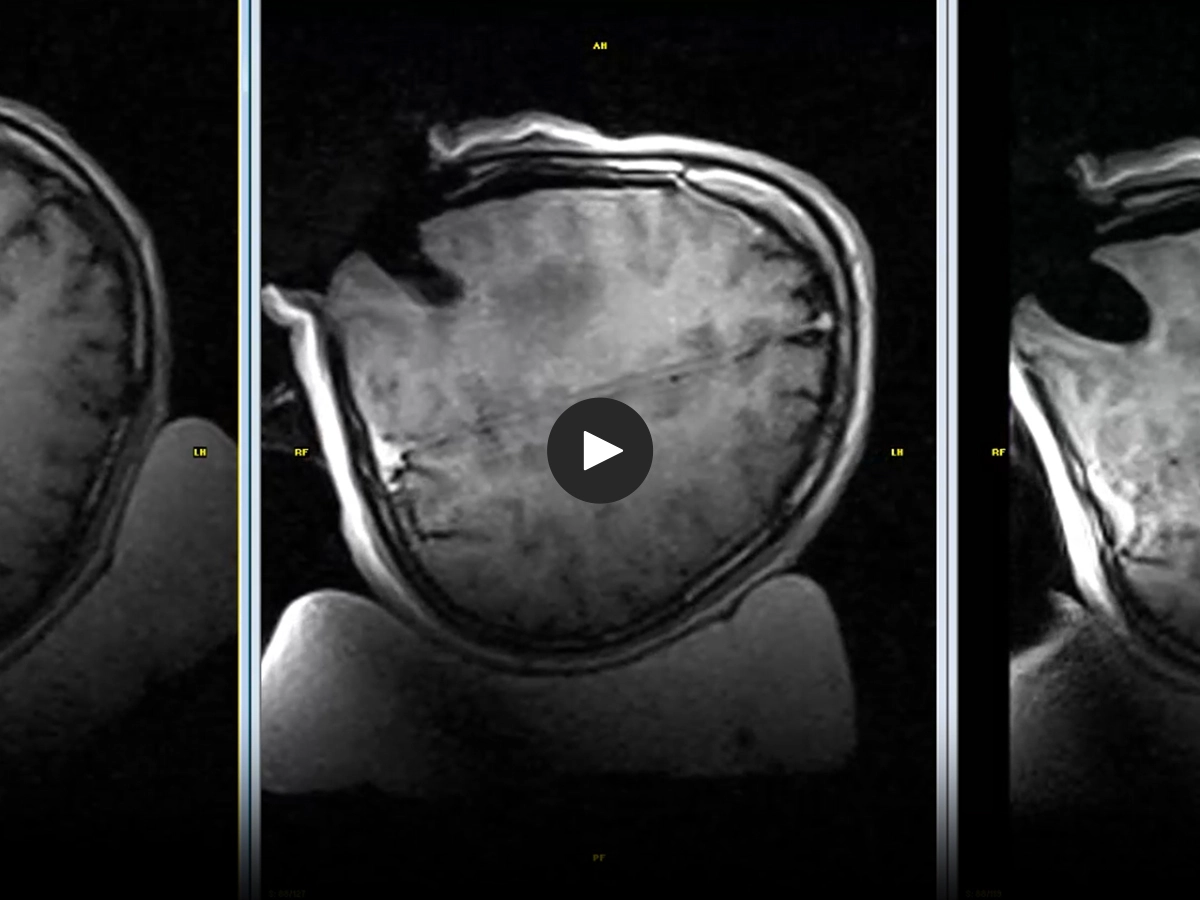

MRI is available during surgery, providing images at the crucial moment in addition to the post-operative follow-up

The patient stays at the center: both surgical and MRI procedures are performed on a single integrated bed system - no transfer required

What is truly innovative about I‑Genius is its ability to provide intraoperative imaging at every stage of neurosurgery. This allows the surgeon to resect the lesion, immediately verify the result, reassess how to proceed with precision and safety, and then confidently continue the procedure.